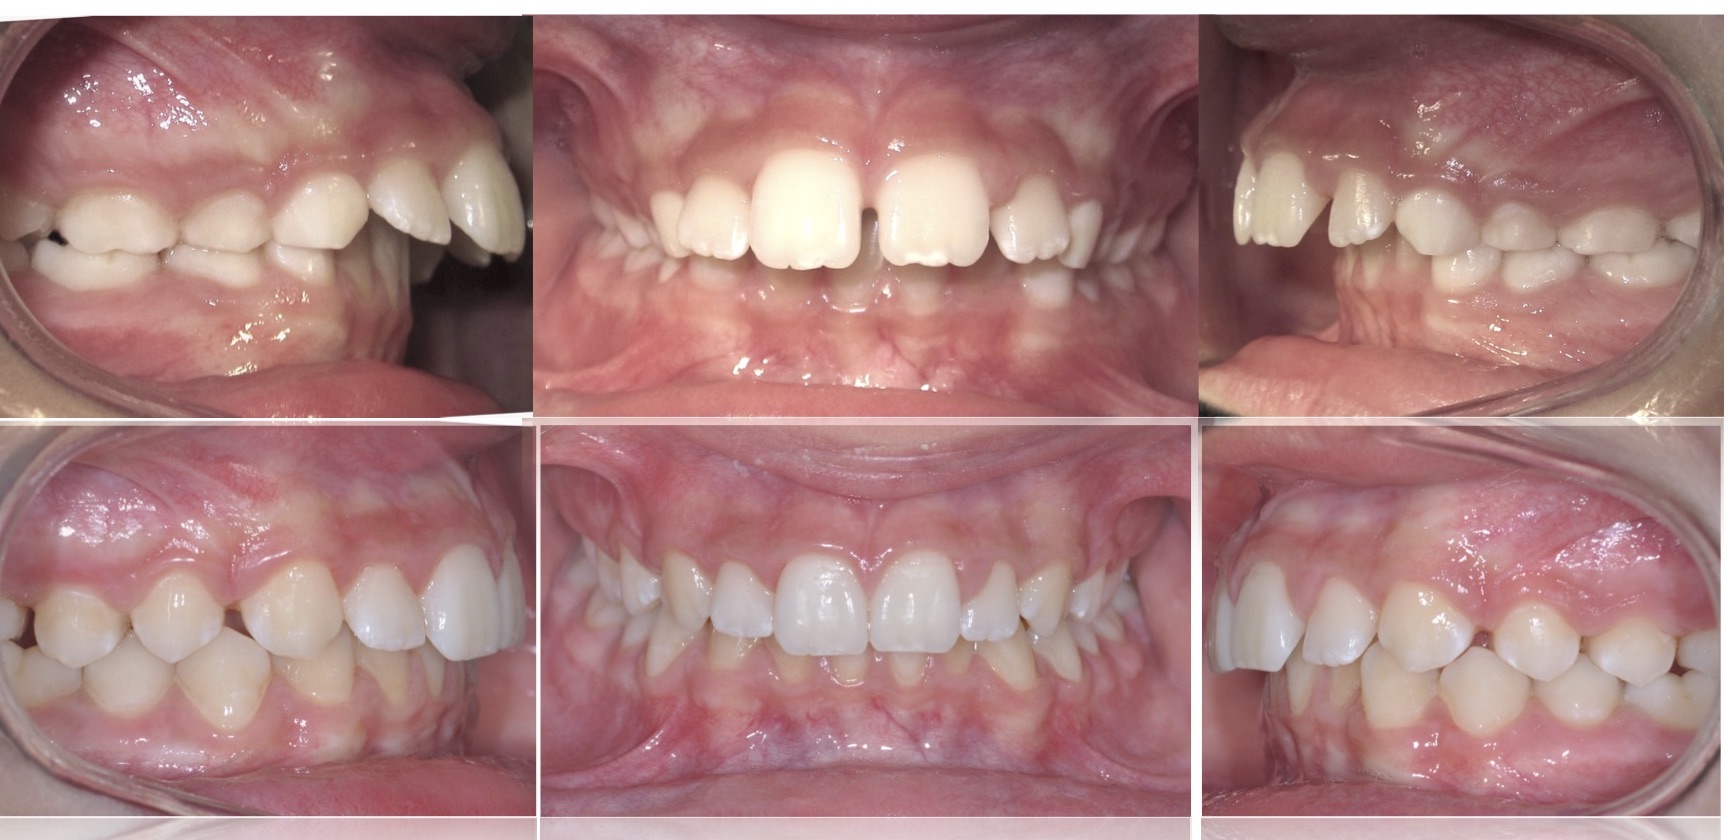

Hanno solitamente pelle color verde spento, grossolani capelli scuri, piccoli occhi rossi e denti sporgenti, simili a zanne Gli orchi considerano le cicatrici un segno di distinzione e spesso le utilizzano come una forma d'arte Nomi Maschili Arkus, Carrug, Felzak, Murdut, Prabur Femminili Durra, Grillgiss, Ilyat, Krugga, Leffit, Olbin. Denti sporgenti esempio di correzione 3 Febbraio 19 7 Dicembre 17 di Dr Tito Mattia Bordino I denti sporgenti ( video ) sono un problema estetico che i pazienti non accettano. Il termine denti sporgenti viene utilizzato generalmente per indicare una condizione in cui i denti anteriori, solitamente molto grandi, sporgono sul labbro andando a coprire anche il labbro inferiore.

Denti Sporgenti Esempio Di Correzione Ortodonzia Torino